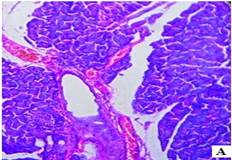

The histopathological studies of the pancreatic tissues are shown in (fig. 3). Normal rats showed the normal architecture of the pancreas with the preserved islet of Langerhans cells (fig. 3A). Induction of diabetes using Streptozotocin resulted in hyalinization of islets of Langerhans cells with focal mild degenerative changes, mild fibrosis, dilated and congested vessels along with focal chronic inflammatory cell infiltrate in diabetic rats (fig. 3B). HFT control rats showed mild edema of islets of Langerhans cells, thick-walled and congested vessels, focal lymphocytic infiltrate exhibiting focal edematous changes (fig. 3C). The abnormal histopathology of the pancreas due to Streptozotocin-induced diabetes was reversed in the Glibenclamide, and EAFBN treated diabetic animals.

The recovery of standard Glibenclamide treated group was evident as near normal architecture with preserved islet cells and mild edema (fig. 3D). The resulted in EAFBN (100 mg/kg, 200 mg/kg & 400 mg/kg) treated groups mild hyalinization islets of langerhans cells with focal mild degenerative changes when compared to untreated diabetic rats. It can be noted that the islets of langerhans cells regenerated in the treatment groups (fig. 3E,3F& 3G).

Fig. 3: Histology of control and treated rat pancreas of antidiabetic studies. A) Control rat, B) Diabetic control, C) HFT control, D) Standard, E) EAFBN (100 mg/kg), F) EAFBN (200 mg/kg) and G) EAFBN (400 mg/kg)